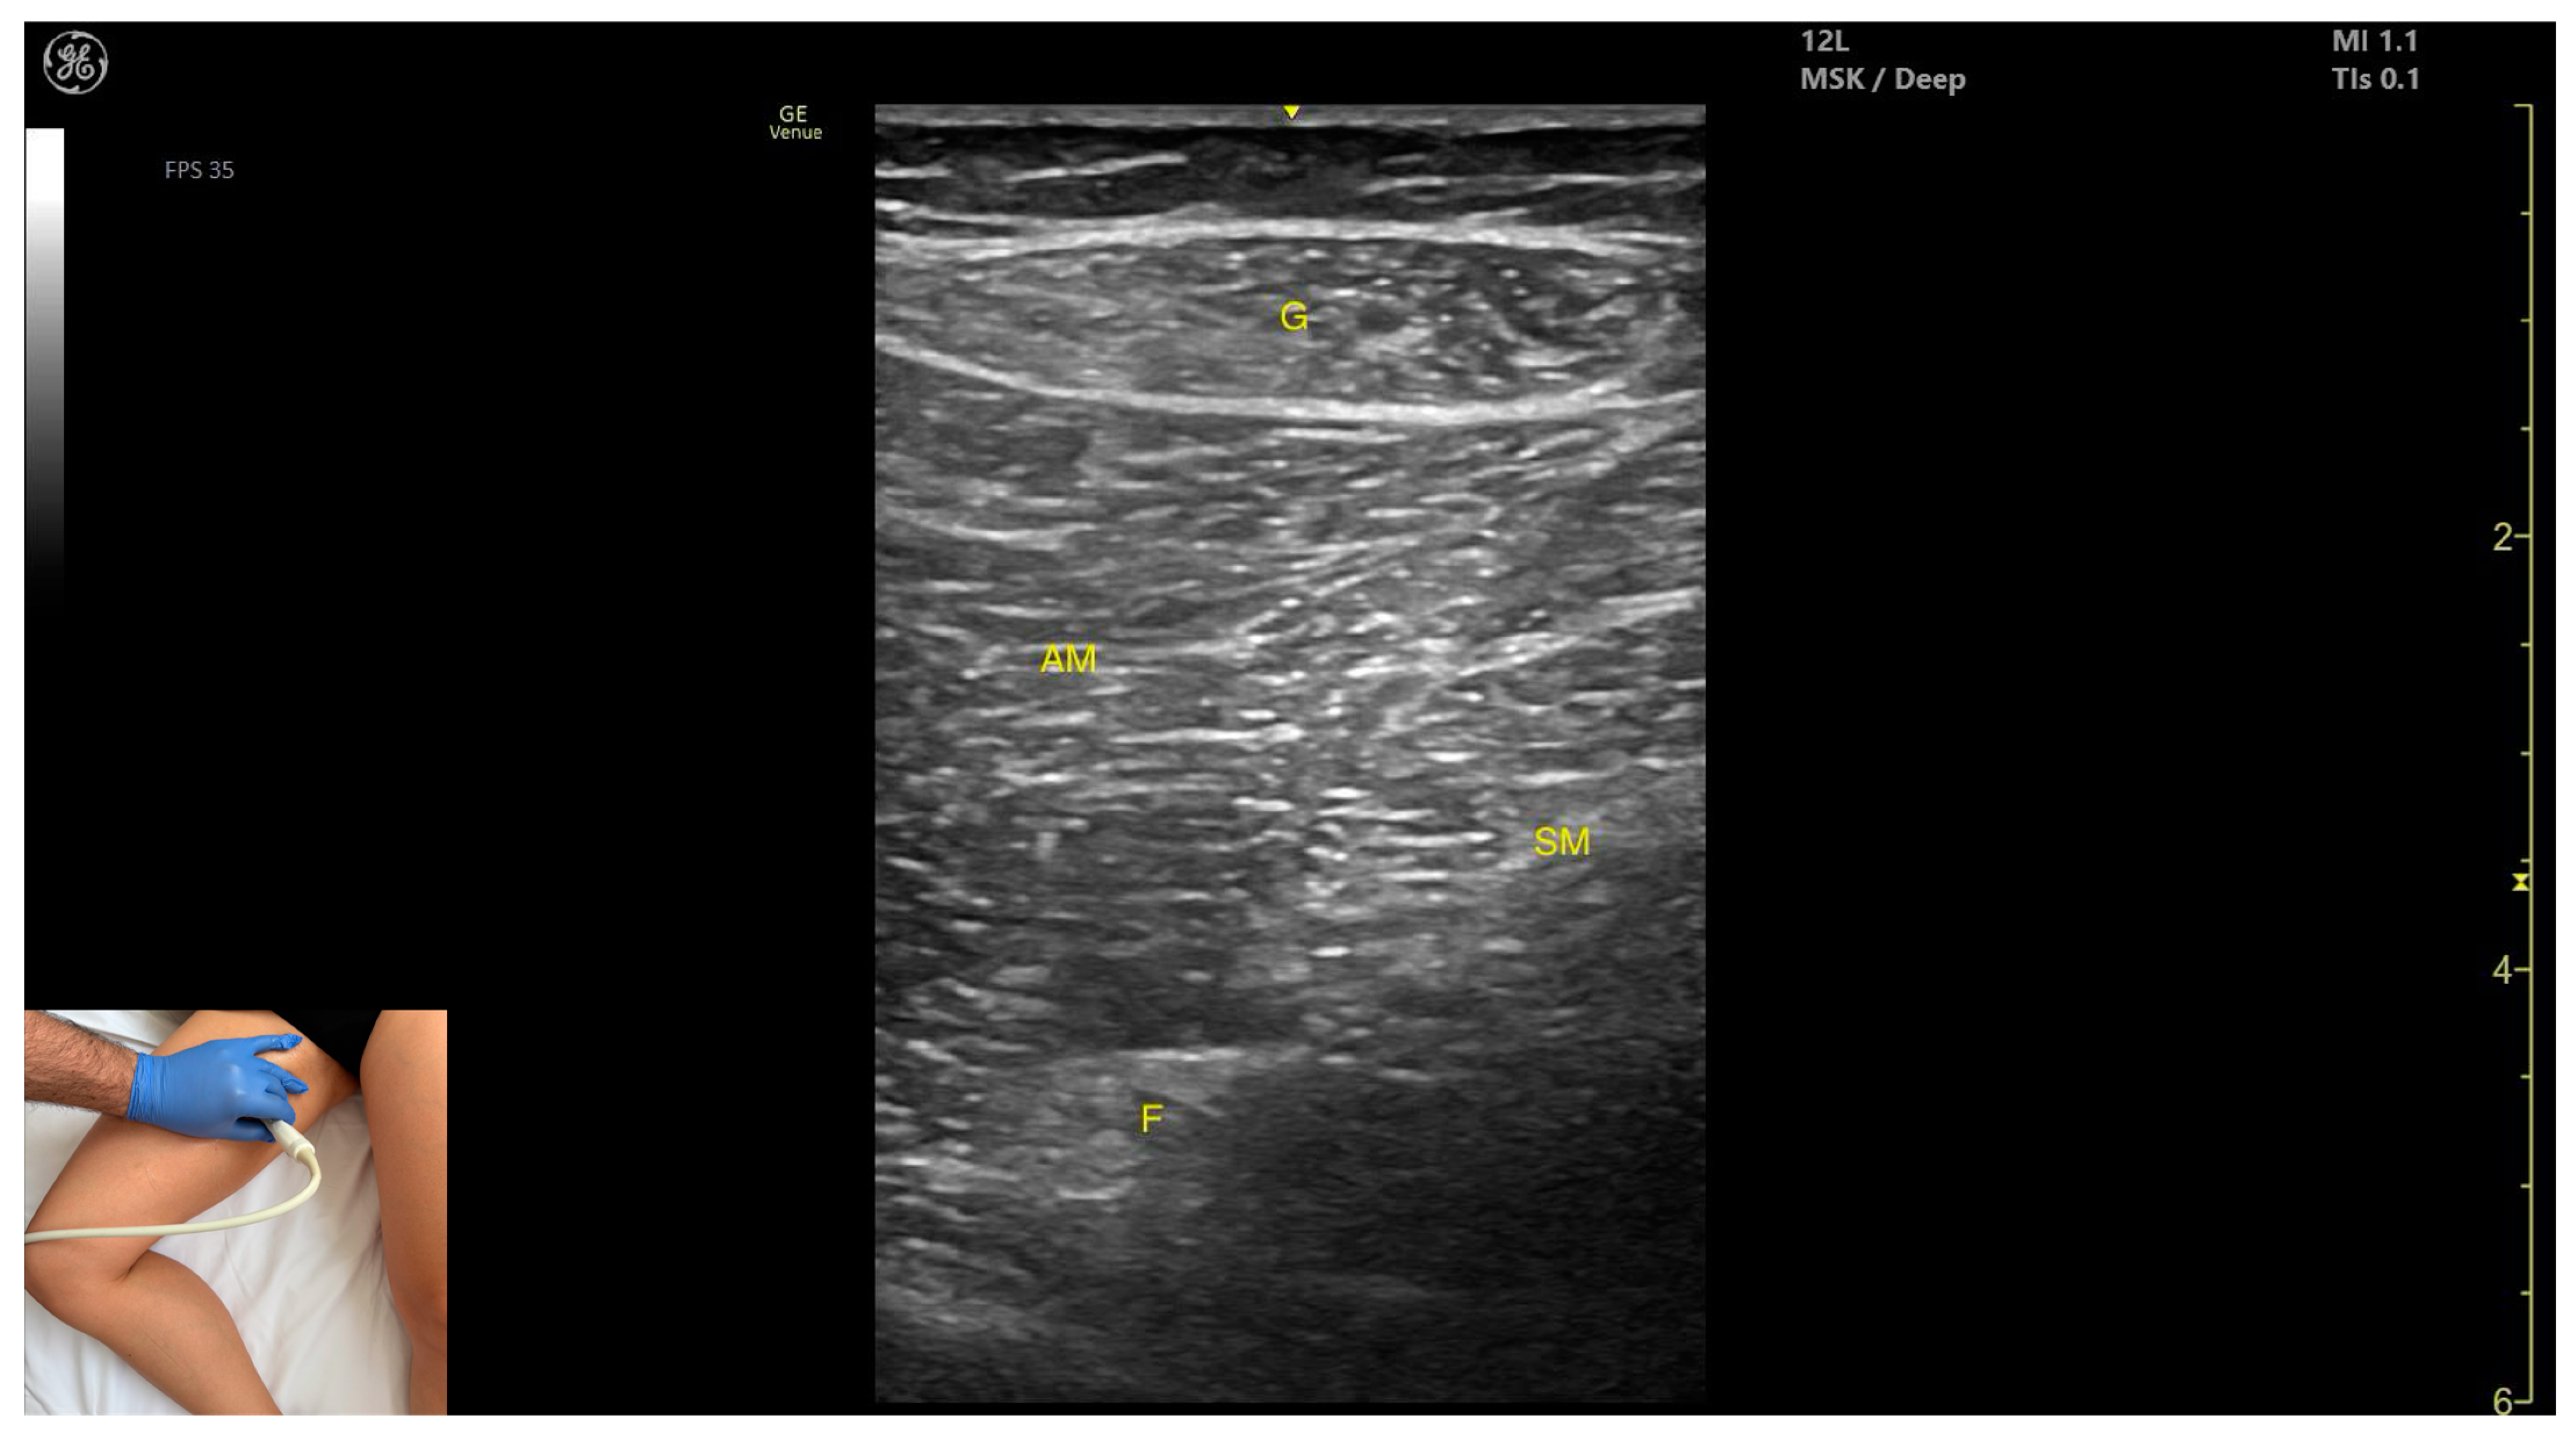

3.6. Gracilis (G)

3.6.2. Ultrasound Identification

3.6.3. Key Ultrasound Landmarks

- Muscle position: It is the most superficial and medial muscle mass of the thigh. Lateral and deep to the G lies the adductor longus, while medial and deep to the G lies the semimembranosus.

- External fascia: It presents a well-defined fascia that separates it from the subcutaneous plane and from the adductor magnus, adductor longus, and semimembranosus, which is relevant for BoNT-A injections.

- Dynamic evaluation: During dynamic evaluation, scanning toward the distal third of the medial thigh, the following are observed: the relationship between the G and adductor magnus remains consistent, the adductor longus disappears from view, the Sart muscle appears, joining the gracilis, and the adductor canal becomes visible, located deep and lateral to the gracilis. In the distal third of the medial thigh, the G is positioned lateral to the semitendinosus. Scanning further distally beyond the knee joint, the tendons of the G, sartorius, and semitendinosus converge to form the pes anserinus on the medial aspect of the proximal tibia. Muscle contraction is visible during hip adduction, knee flexion, and internal rotation maneuvers.

3.6.4. Clinical Implications and Injection Strategy

3.8. Adductor Magnus (AM)

3.8.2. Ultrasound Identification

3.8.3. Key Ultrasound Landmarks

- Muscle morphology: It is the largest and deepest muscle of the adductor group.

- Muscle position: It is the first muscle mass superficial to the femoral cortex at this level. It is covered superficially by the gracilis muscle; medial to it lies the semimembranosus.

- External fascia: It has a well-defined fascia separating it from the gracilis and semimembranosus, supporting safe BoNT-A injections.

- Dynamic evaluation: During dynamic evaluation, scanning distally toward the knee joint, a reduction in muscle bulk is observed in both the AM and gracilis. Muscle contraction is visible during hip adduction and hip flexion maneuvers.

3.8.4. Clinical Implications and Injection Strategy

| Gracilis | Proximal third of medial thigh | Adductor longus (deep and lateral), adductor magnus (deep), and semimembranosus (deep and medial) | Transverse scan with the hip abducted, externally rotated, and semi-flexed and the knee in semi-flexion | Visualize gracilis as most superficial medial muscle |

| Adductor Magnus | Proximal third of medial thigh | Gracilis (superficial) and semimembranosus (medial) | Transverse scan with the hip abducted, externally rotated, and semi-flexed and the knee in semi-flexion | Identify deep muscle mass below gracilis |